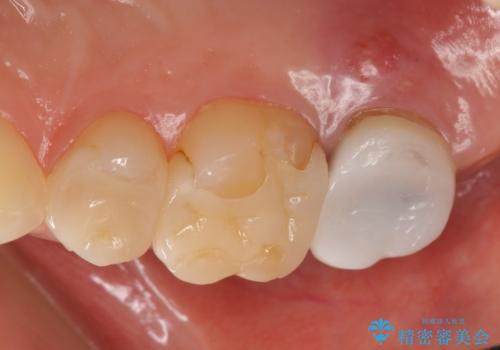

- 右上6、7の詰め物、被せ物を治して欲しいといらっしゃった方の症例です。

右上6は虫歯を除去し、右上7は再根管治療後、オールセラミッククラウンによる補綴を行いました。